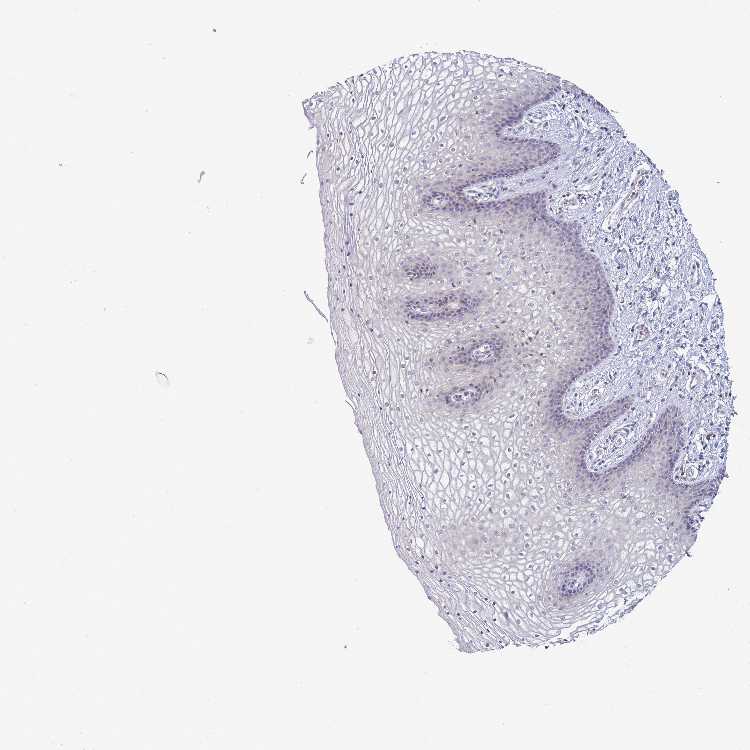

TISSUE PRIMARY DATA VAGINA Show tissue menu

VAGINA - Antibody stainingi

Antibody staining in the annotated cell types in the current human tissue is reported as not detected, low, medium, or high, based on conventional immunohistochemistry profiling in selected tissues. This score is based on the combination of the staining intensity and fraction of stained cells.

Each image is clickable and will lead to virtual microscopy that enables deeper exploration of all samples and also displays staining intensity scores, fraction scores and subcellular localization as well as patient and tissue information for each sample.

Antibody HPA046039

Squamous epithelial cells Not detected